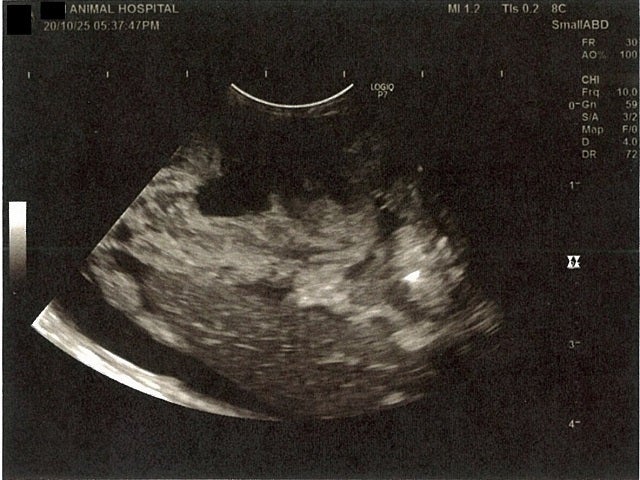

《心臓周りの胸部以外の全ての腹部で腹水がみられるとの診断です》

大網という部分で内臓を包む膜のようなものです。その周りに腹水が溜まっています。

膀胱周りに腹水が確認できるエコー写真